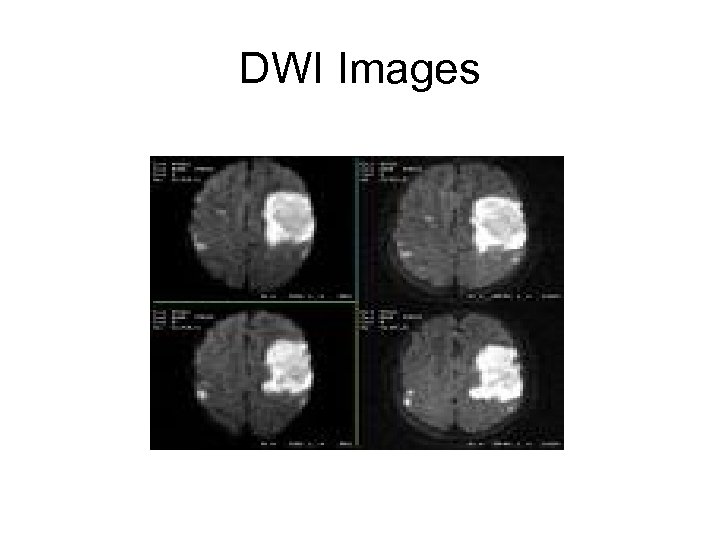

DWI Images